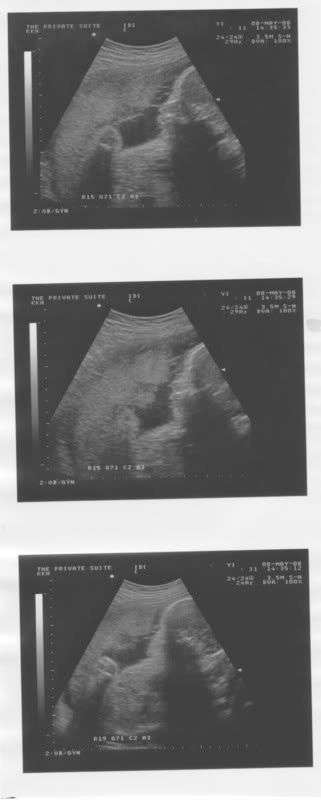

So I was scanned and everyone squeezed in that corner to have a glimpse of Peanut..

Amazingly enough, Peanut kept really still throughout the scan!!

It amazes me cos Peanut always move about during previous scans..

In fact, Peanut was so still that my Mummy told my gynae, 'Wow..Baby is really quiet today.'

To that, Peanut gave one hard kick and that's it..

So gynae played around with the scan thingy..Peanut was not cooperating by closing his/her legs..Poor gynae had to even poke and tap at Peanut to get the legs to open..Hahaha!!!

Finally, gynae confirmed Peanut's gender..Everyone was ecstatic.. :)

Wanna see Peanut?

The more I look at the pic, the more I grow to love my cheeky Peanut..

Our Peanut..*love*

If you can look closely at the pic, you could see that my Peanut has pouty lips like DH and tembam cheeks like me..Hehehe!!

Oh!! I read that Peanut should weigh about 800 grams..

Guess how much Peanut weighs now..

More than 1 kg..